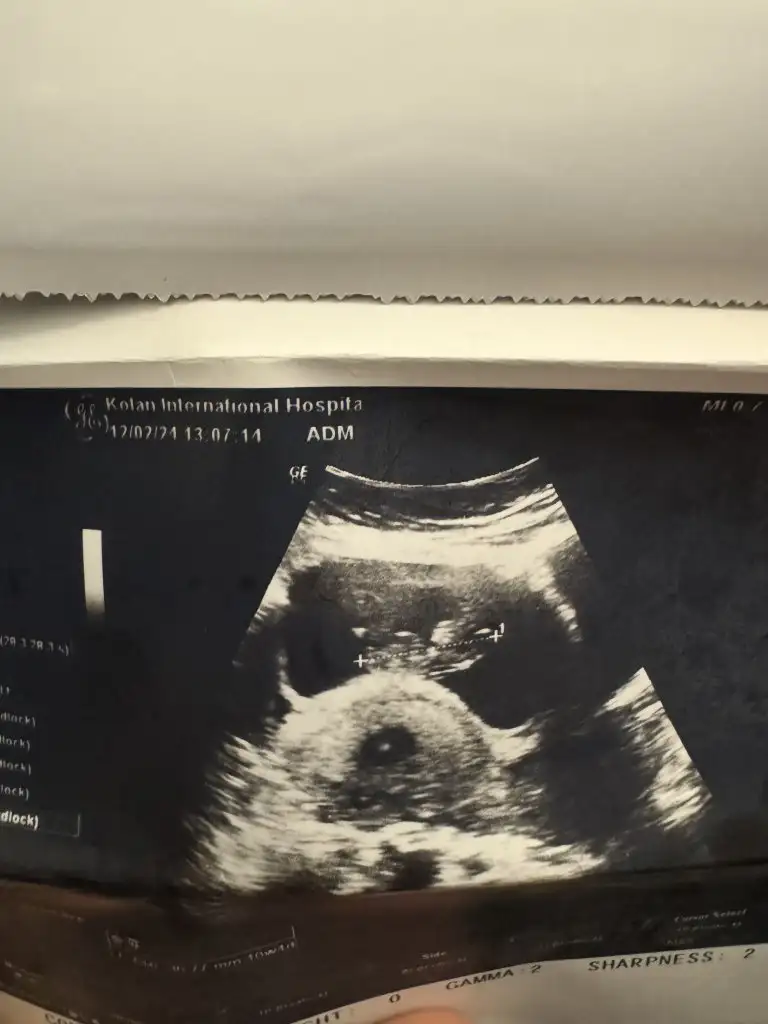

Selam bizede bakarmısınız ilki 6haftalık vajinal diğeri 7+3 karından bakıldı

Eklentiler

• IMG_8431.webp

IMG_8431.webp

31 KB · Görüntüleme: 87

• 45a639a2-0c77-4877-8f07-fa6d62c7beef.webp

45a639a2-0c77-4877-8f07-fa6d62c7beef.webp

29,6 KB · Görüntüleme: 82